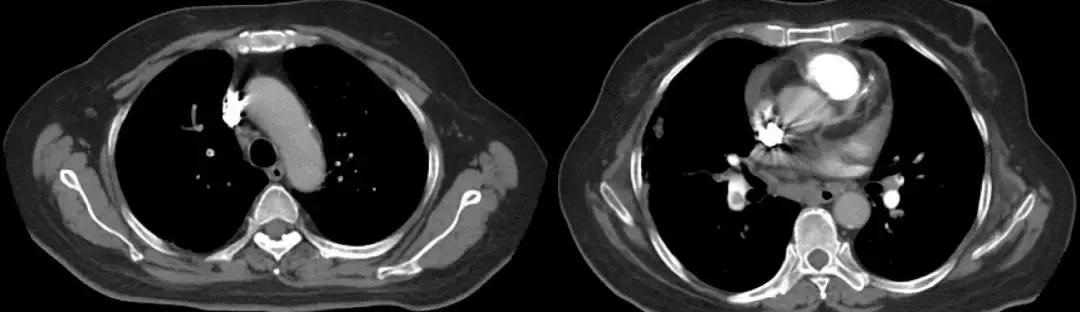

1天前急救车于我院急诊,血常规提示白细胞明显升高,胸部CT(2017-3-15):两肺感染,右肺上叶中叶膨胀不全,两肺间质改变,两肺肺气肿;急诊给予「头孢哌酮舒巴坦联合万古霉素」抗感染治疗,面罩10L/分吸氧维持血氧饱和度在85~95%之间,现为进一步诊治以「重症肺炎」收住我科。

CT:2018-3-15

既往有高血压病,患高血压10余年,平日未监测血压,最高达170/100mmHg,未规律服用降压药,血压控制差。2年前诊断结肠癌,行手术治疗,术后化疗6个疗程(具体用药不详),结肠癌术后逐渐出现活动后呼吸困难,并进行性加重,未诊治。吸烟40余年,1~2包/日,戒烟2年;家族史无特殊。